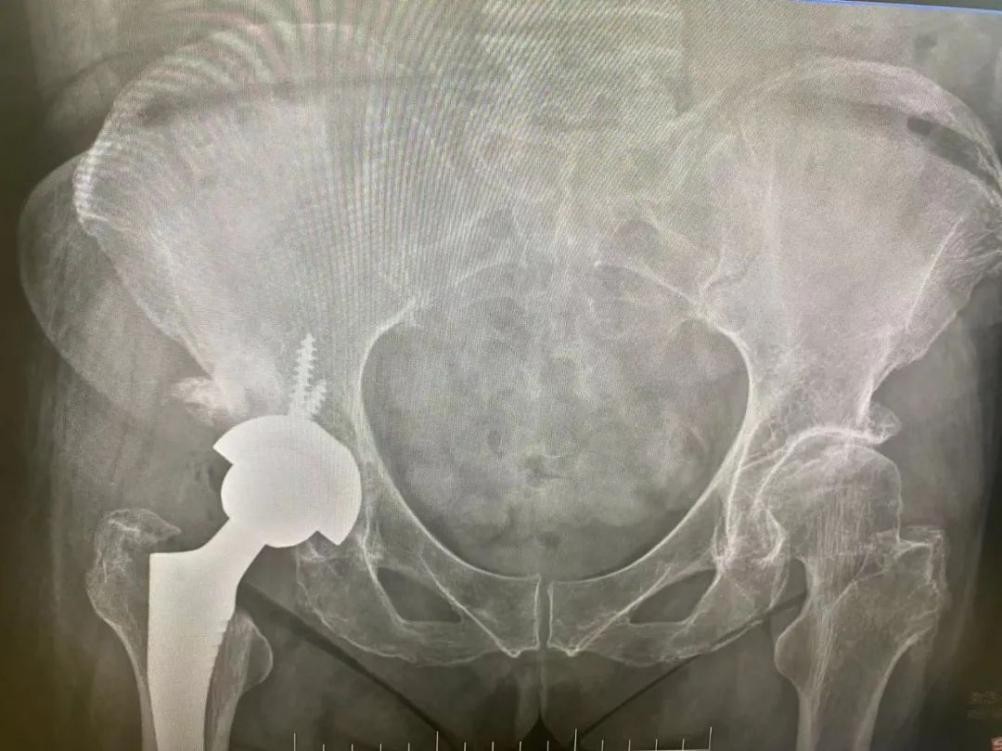

8 月中旬,由骨科康长周主任领衔的股骨头坏死诊疗团队为毛阿姨进行了人工全髋关节置换术,术后病理证实均股骨头坏死诊断准确。

在之后的随访中,了解到目前毛阿姨恢复良好,已经能较为自由地行走。